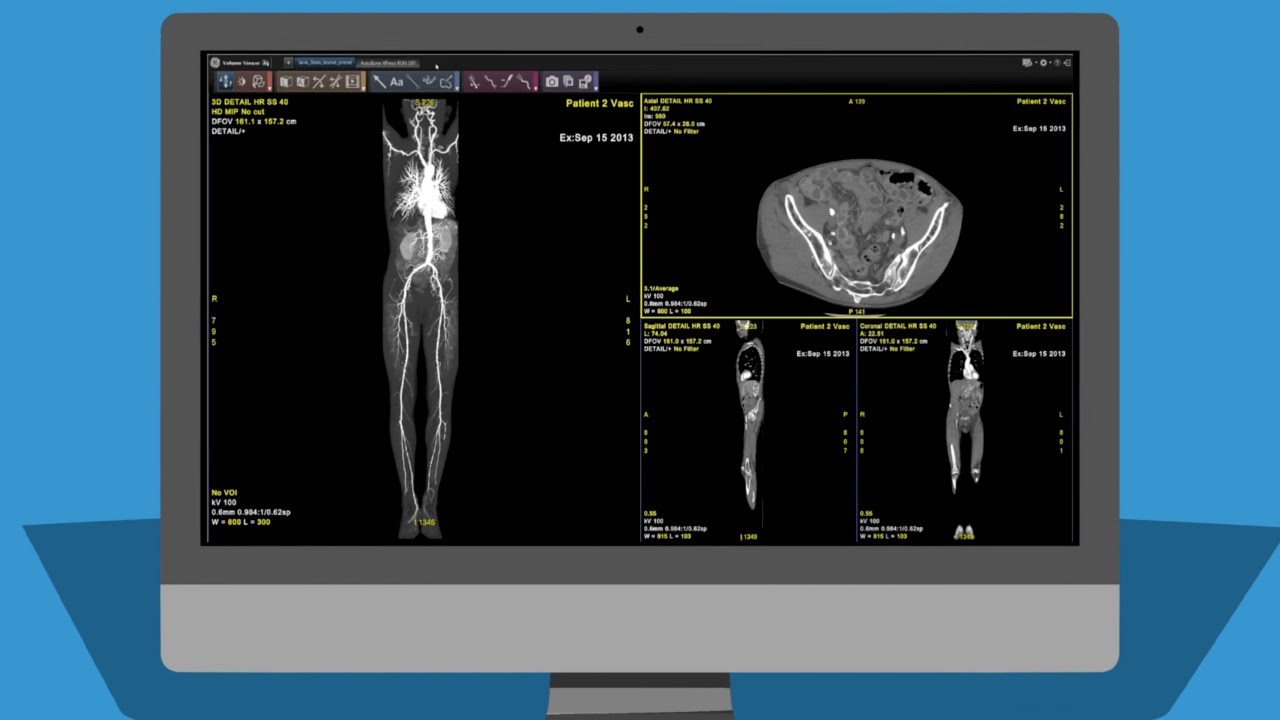

Through the partnership, both companies will be offering radiologists specializing in cardiology, oncology, orthopedics, neurology, and other areas an end-to-end GE Healthcare/Formlabs bundle for producing anatomical models. Included within the bundle are Formlabs 3D printers and materials, and GE Healthcare’s Advantage Workstation (AW) advanced visualization software for preparing the 3D models for printing.

“When time is of the essence, GE Healthcare solutions help clinical imaging specialists get the diagnosis correct quickly and push the critical information they create into the hands of the broader care team,” commented R. Scott Rader, general manager of GE Healthcare Additive Solutions. “The virtual reality renderings clinical imagers see every day in radiology reading rooms on AW can now be exported via AW 3D Suite in seconds, imported into Formlabs PreForm, and printed right at the site of care to add the sense of touch to what members of the care team see. “

GE Healthcare’s AW advanced visualization tools are specifically designed for the medical community, to help radiologists create 3D models of normal and pathological anatomy using automation techniques. Leveraging a diagnostic workflow, AW is intended to speed up the often labor intensive process of preparing image data into 3D printable files. This will reportedly help to reduce the time it takes to create STL and OBJ files required for 3D models from hours to minutes.

Key to the AW software is that it is compatible with all imaging modalities, including CT, MR, PET, SPECT and Interventional. Bringing these techniques together, clinicians are able to boost their productivity with over 55 clinical applications, presented on a consistent user interface that can be viewed via a Workstation, RIS/PACS, laptop, or PC.